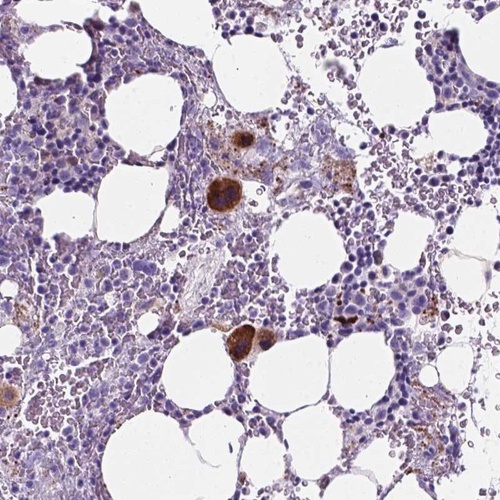

Immunohistochemical staining of human bone marrow shows cytoplasmic positivity in megakaryocytes.